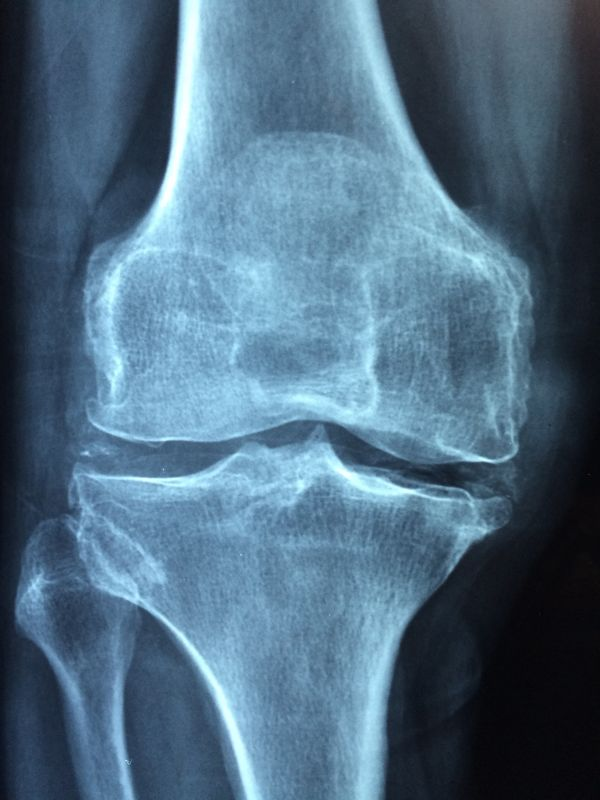

몇가지 말고는 퇴행성 관절염의 증세와 똑같습니다. 퇴행성 관절염을 설명하기 위해 이제껏 무릎 위주로 설명했지만, 무릎만이 아니라 우리 몸 모든 관절에서 '늙어가는 퇴행성 변화'는 진행합니다.

늙어가면서 발목, 발가락, 어깨, 팔꿈치, 손목, 손가락 등 모든 관절에서 퇴행성 관절염이 진행될 수 있고, 동시에 여러 관절에도 생길 수 있습니다. 그래서 여러 관절에 관절염이 생겨난다는 이유로 류마티스라고 진단해서는 안 되겠죠.

무릎의 경우만 해도 대부분 환자들이 양쪽 무릎 모두의 증세를 호소합니다. 한쪽 무릎만 늙어가는 게 아니기 때문이죠. 한쪽 무릎의 증세가 더 뚜렷하게 느껴져서 그쪽만 아픈 경우라도, 퇴행성 변화는 반대편 무릎에도 진행되고 있습니다.

대부분 퇴행성 관절염의 증세는 차이가 있긴 하지만 양쪽 관절에 대칭성을 띠고 생겨납니다. 그러니 대칭성 관절염 소견이 있다고 해서, 류마티스 관절염 진단 기준이 될 수는 없습니다.

나이가 들어가며 오랫동안 서서히 변화가 일어나는 대부분의 퇴행성 관절염 환자와 달리, 관절의 퇴행성 변화가 매우 빨리 심하게 진행하는 경우도 있습니다.

이런 환자들은 통증도 심하고 밤새 굳어지는 정도도 심해서 아침에 특히 더 아프고, 관절의 이런 변화들 때문에 활동이 어려워지면서 관절 운동범위 역시 빠르게 제한되고 근육도 빠르게 가늘어져서, 급기야 보행을 하지 못하게 되기도 합니다.